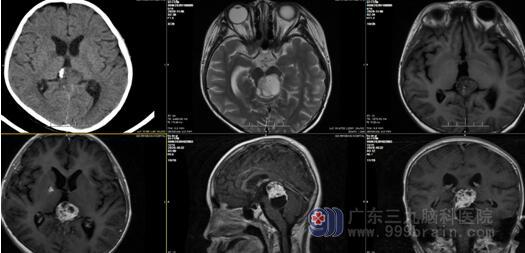

查体:神志清楚,对答切题,双瞳孔等大同圆,直径4.0mm,对光反射迟钝,右侧额部切口陈旧直切口,愈合良好,颈略抵抗,四肢肌力4级,肌张力正常,生理反射存在,病理征未引出。辅助检查: 头颅MR提示:1.松果体区占位性病变范围较前稍增大;2.右侧额叶术道条状强化;3.幕上梗阻性脑积水较前缓解,间质性脑水肿已不明显。

患者入院后予完善1.血、尿、粪常规、肝肾心功能、凝血功能等。2.胸片、心电图、B超等,未见明显异常,2020-11-08,3.0TMR平扫见:拟松果体区生殖细胞肿瘤行第三脑室底造瘘术及放化疗后复查,对比PACS图像(2020-10-22MR),现:1.松果体区占位性病变强化程度稍减低;2.右侧额叶术道条状强化强化较前缓解。完善术前准备后于2020年11月09日在全麻下行“经Poppen入路松果体区肿瘤切除术”,术程顺利,术中见肿瘤包膜完整,质韧,血供丰富,囊实性改变,可见流沙样物质及钙化组织,脑干略有粘连。给予仔细分离肿瘤并全切除。术后予止血、预防癫痫及营养支持等密切观察治疗。

术前影像资料: